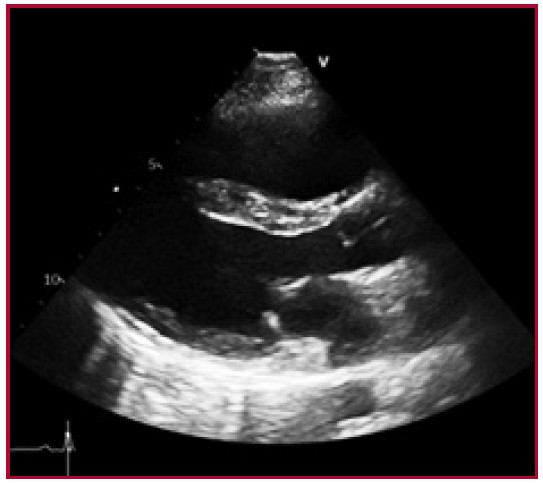

Se describe el caso de una paciente de sexo femenino de 20 años con diagnóstico previo de enfermedad mixta del tejido conectivo en 2018, sin seguimiento en los últimos 18 meses, tiroiditis de Hashimoto y bronquiectasias. Acudió a Guardia Externa por dolor abdominal, náuseas y diarrea. A su ingreso se constataron signos de insuficiencia cardíaca derecha (edemas en miembros inferiores, ingurgitación yugular sin colapso inspiratorio, reflujo hepatoyugular positivo y hepatomegalia), aumento de la intensidad del segundo ruido cardíaco a expensas del componente pulmonar, y soplo sistólico en foco tricuspídeo. El estudio diagnóstico inicial incluyó un electrocardiograma con signos de sobrecarga de cavidades derechas y bloqueo completo de rama derecha, y radiografía de tórax con aumento del segundo arco pulmonar derecho e índice cardiotorácico conservado. En el ecocardiograma Doppler se observó dilatación de cavidades derechas, disfunción grave del ventrículo derecho, insuficiencia tricuspídea grave con velocidad de regurgitación pico mayor que 4,5 metros por segundo (m/s), presión sistólica de la arteria pulmonar (PSAP) de 105 mm Hg, presión media de la arteria pulmonar (PAPm) de 55 mm Hg y derrame pericárdico leve. (Figura 1). Consecutivamente se realizó cateterismo cardíaco derecho que confirmó el diagnóstico de hipertensión arterial pulmonar (HAP) grave con presión media de aurícula derecha de 11 mm Hg, PAPm de 63 mm Hg, presión de enclavamiento pulmonar de 10 mm Hg, resistencia vascular pulmonar de 21 unidades Woods (UW), gradientes transpulmonar y diastólico de 53 mm Hg y 43 mm Hg respectivamente, gasto cardiaco (GC) de 3,20 L/min , índice cardíaco (IC) de 2,6 L/min/m2, índice de volumen sistólico (IVS) 23 ml/lat/m2, saturación venosa mixta de 65% y saturación arterial de 97%. Por falla ventricular derecha marcada, inició infusión endovenosa continua de furosemida sin respuesta favorable, soporte inotrópico con milrinona a dosis máxima que posteriormente se rotó a levosimendán 0.1 ug/kg/ min y soporte vasopresor con noradrenalina a dosis intermedias. La paciente evolucionó de forma desfavorable con signos de bajo gasto cardíaco y falla grave del ventrículo derecho. Debido a la falta de acceso inmediato a prostanoides parenterales, se realizó septostomía transeptal con balón de forma exitosa (fenestración de 5 mm) (Figura 2). La paciente presentó mejoría del estado clínico, con derivación precoz a un centro de mayor complejidad para valoración pretrasplante e inicio de infusión continua de epoprostenol endovenoso, con dosis en ascenso hasta 12 ng/kg/min, previo destete y suspensión de inotrópicos, e inicio de ambrisentán 10 mg y tadalafilo 10 mg con buena tolerancia. En el ecocardiograma Doppler control presentó dilatación moderada de cavidades derechas, PSAP de 70 mm Hg y solución de continuidad interauricular de 0,9 mm. (Figura 3) El cateterismo cardiaco evolutivo demostró descenso de la PAPm, RVP y mejoría del GC e IC (43 mm Hg, 7,3 UW, 4,8 l/min y 3,6 l/min/m2, respectivamente). Fue valorada por el servicio de Reumatología que confirmó el diagnóstico de lupus eritematoso sistémico por criterios clínicos e inmunológicos y nefritis lúpica grado II por biopsia renal.